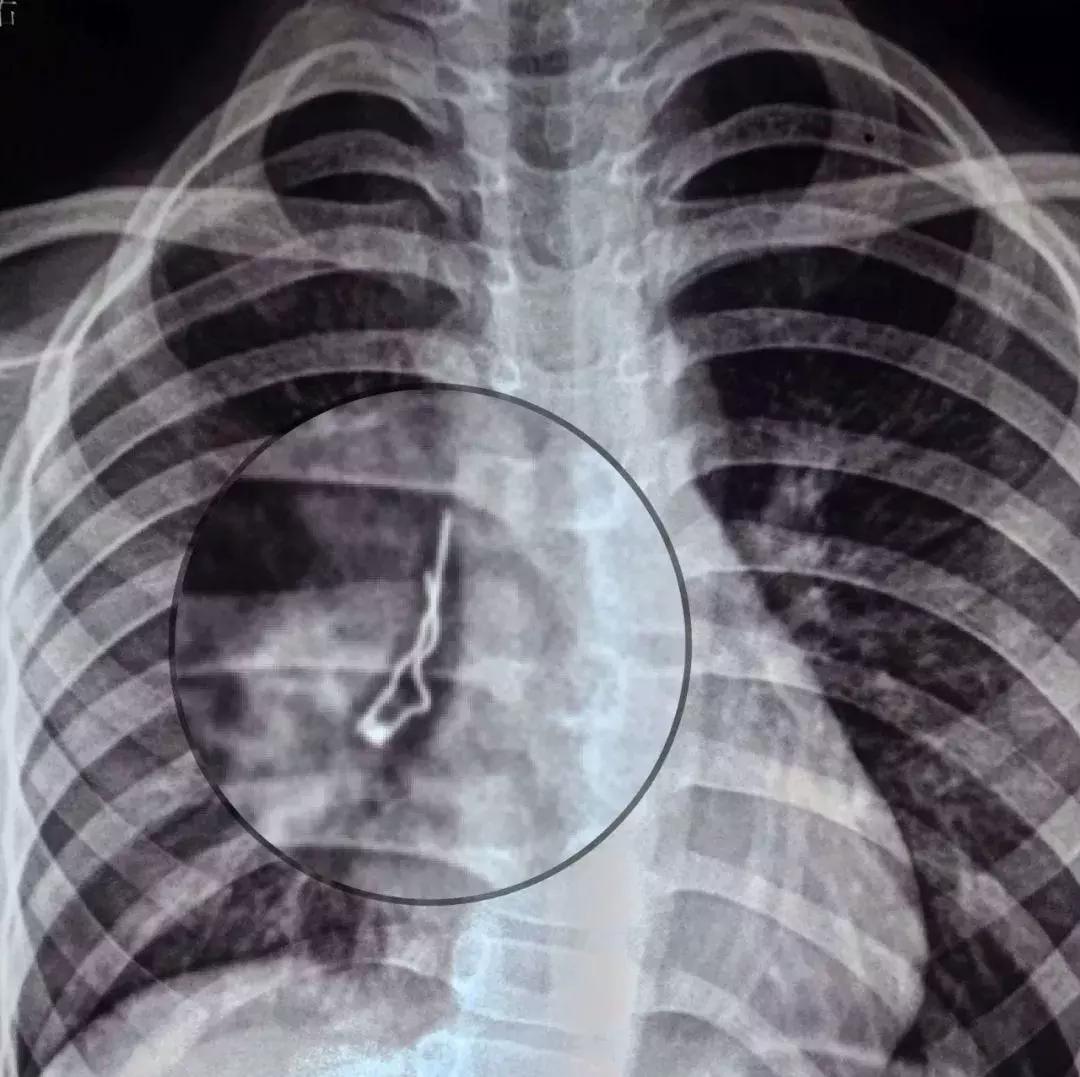

在咸宁一家寄宿小学读书的小路从6月5日开始便有些咳嗽,生活老师给吃了药也不见好转,反而越咳越厉害。12日,爷爷把小宁带到医院就诊,拍片发现肺里有个圆头的异物,上边还有两根细铁丝。小路不肯说吞了什么,当地医院也无法处置,便立刻转诊到省妇幼。

术中,医生发现异物倾斜卡在小路右中间支气管里,尖端已戳破了气管壁粘膜,情况非常危险。经充分评估,医生夹着铁丝的上半段,小心翼翼地将异物取出,这才发现居然是个二极管。医生介绍:“二极管在小路肺里呆了一周,幸而铁丝头朝上,没有扎穿肺部。如果铁丝朝下,随着呼吸运动,尖头随时有可能刺伤气管,引起肺部出血或气胸等严重的致死性并发症。”